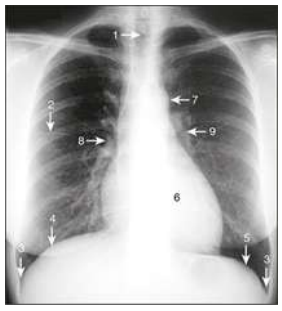

Observe a radiografia de tórax e associe os números

indicados na imagem às estruturas anatômicas listadas:

(__)Hemidiafragma direito

(__)Hilo esquerdo

(__)Arco aórtico

(__)Traqueia

(__)Ângulo costofrênico

Assinale a alternativa que apresenta a sequência correta: